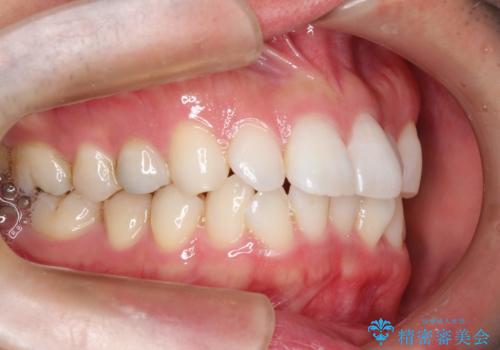

フルリンガル矯正 非抜歯でガタつきを整える

- フルリンガル

- 1年6ヶ月

- フルリンガルワイヤーによる非抜歯治療を計画しました。